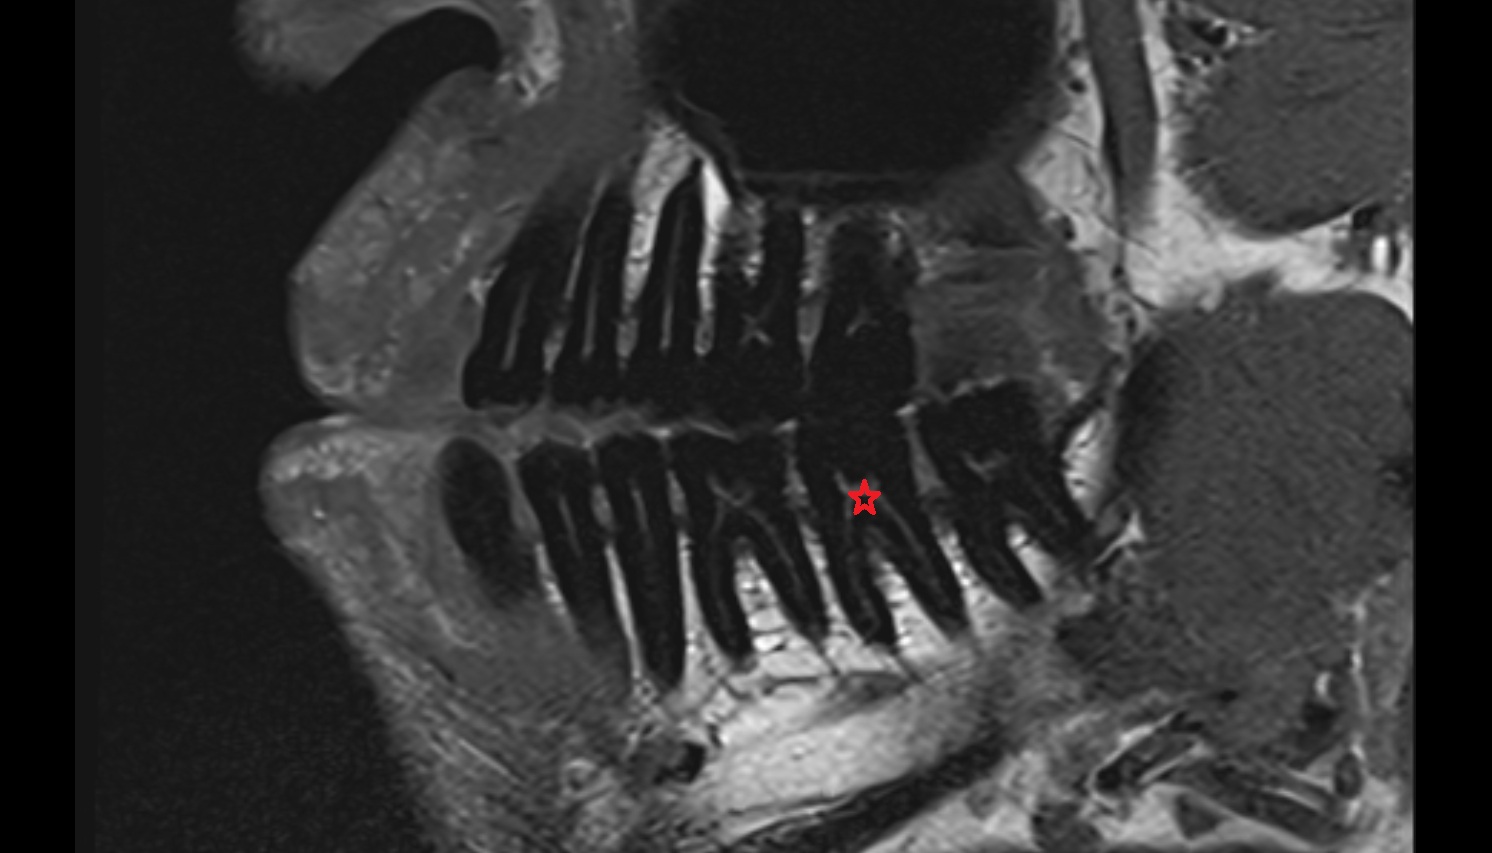

- Root of lower molar tooth

- Lower molar apical foramen

- Upper premolar apical foramen

- Root of upper molar tooth

- Root canal of upper molar tooth

- Dental pulp of upper molar tooth

- Dental pulp of upper premolar tooth

- Root canal of upper premolar tooth

- Root canal of upper canines tooth

- Enamel of upper molar tooth

- Enamel of upper incisor tooth

- Enamel of lower premolar tooth

- Dental pulp of lower molar tooth

- Root canal of lower premolar tooth

- Lower premolar apical foramen

- Dental branches of inferior alveolar artery, vein, & nerve

- Alveolar process of maxilla

- Superior dental plexus